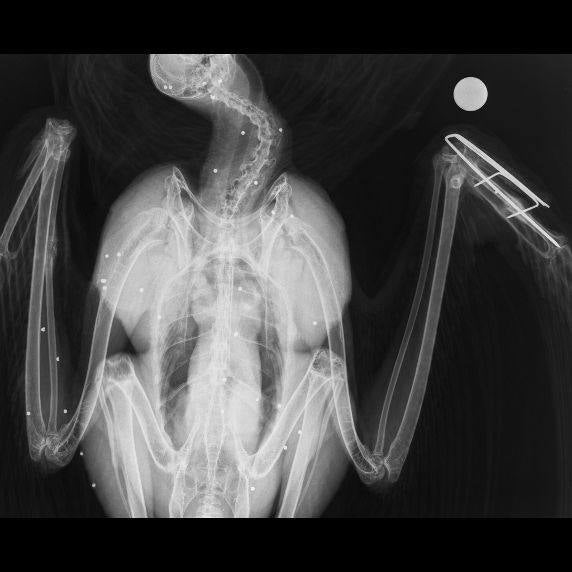

El 2 de febrero de 2022 ingresaba en el hospital de AMUS Orel, un ejemplar juvenil de Águila imperial tras ser disparado en la provincia de Badajoz. En la radiografía se contabilizaron cerca de cincuenta perdigones de plomo.

Radiografía en la que se evidencian los perdigones de plomo del disparo. CEDIDA